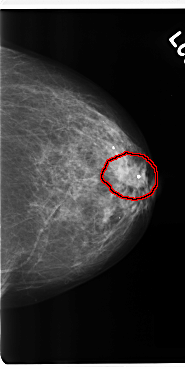

C_0206_1.LEFT_CC

FILE: C_0206_1.LEFT_CC.OVERLAY

TOTAL_ABNORMALITIES 1

ABNORMALITY 1

LESION_TYPE MASS SHAPE IRREGULAR MARGINS SPICULATED

ASSESSMENT 4

SUBTLETY 5

PATHOLOGY MALIGNANT

TOTAL_OUTLINES 1

BOUNDARY